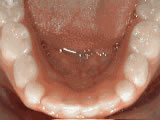

Spacing of teeth

Before

Before After

AfterPatient was bothered by the spaces between his teeth. Braces closed the spaces and gave him an ideal bite in 24 months. Special glued-in retainers help keep the spaces closed.